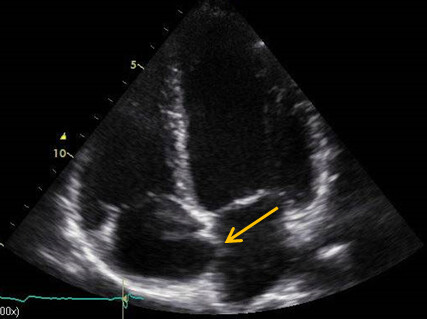

Im Farbdoppler fiel ein minimaler Links-Rechts-Shunt auf der Vorhofebene auf, wobei dieser Befund evtl. auch einem Artefakt entsprechen konnte (Abb. 1B). Rechtsherzbelastungszeichen ließen sich nicht dokumentieren.

Abb. 2: Rechtsherz Eckokardiografie, Credit: Perings